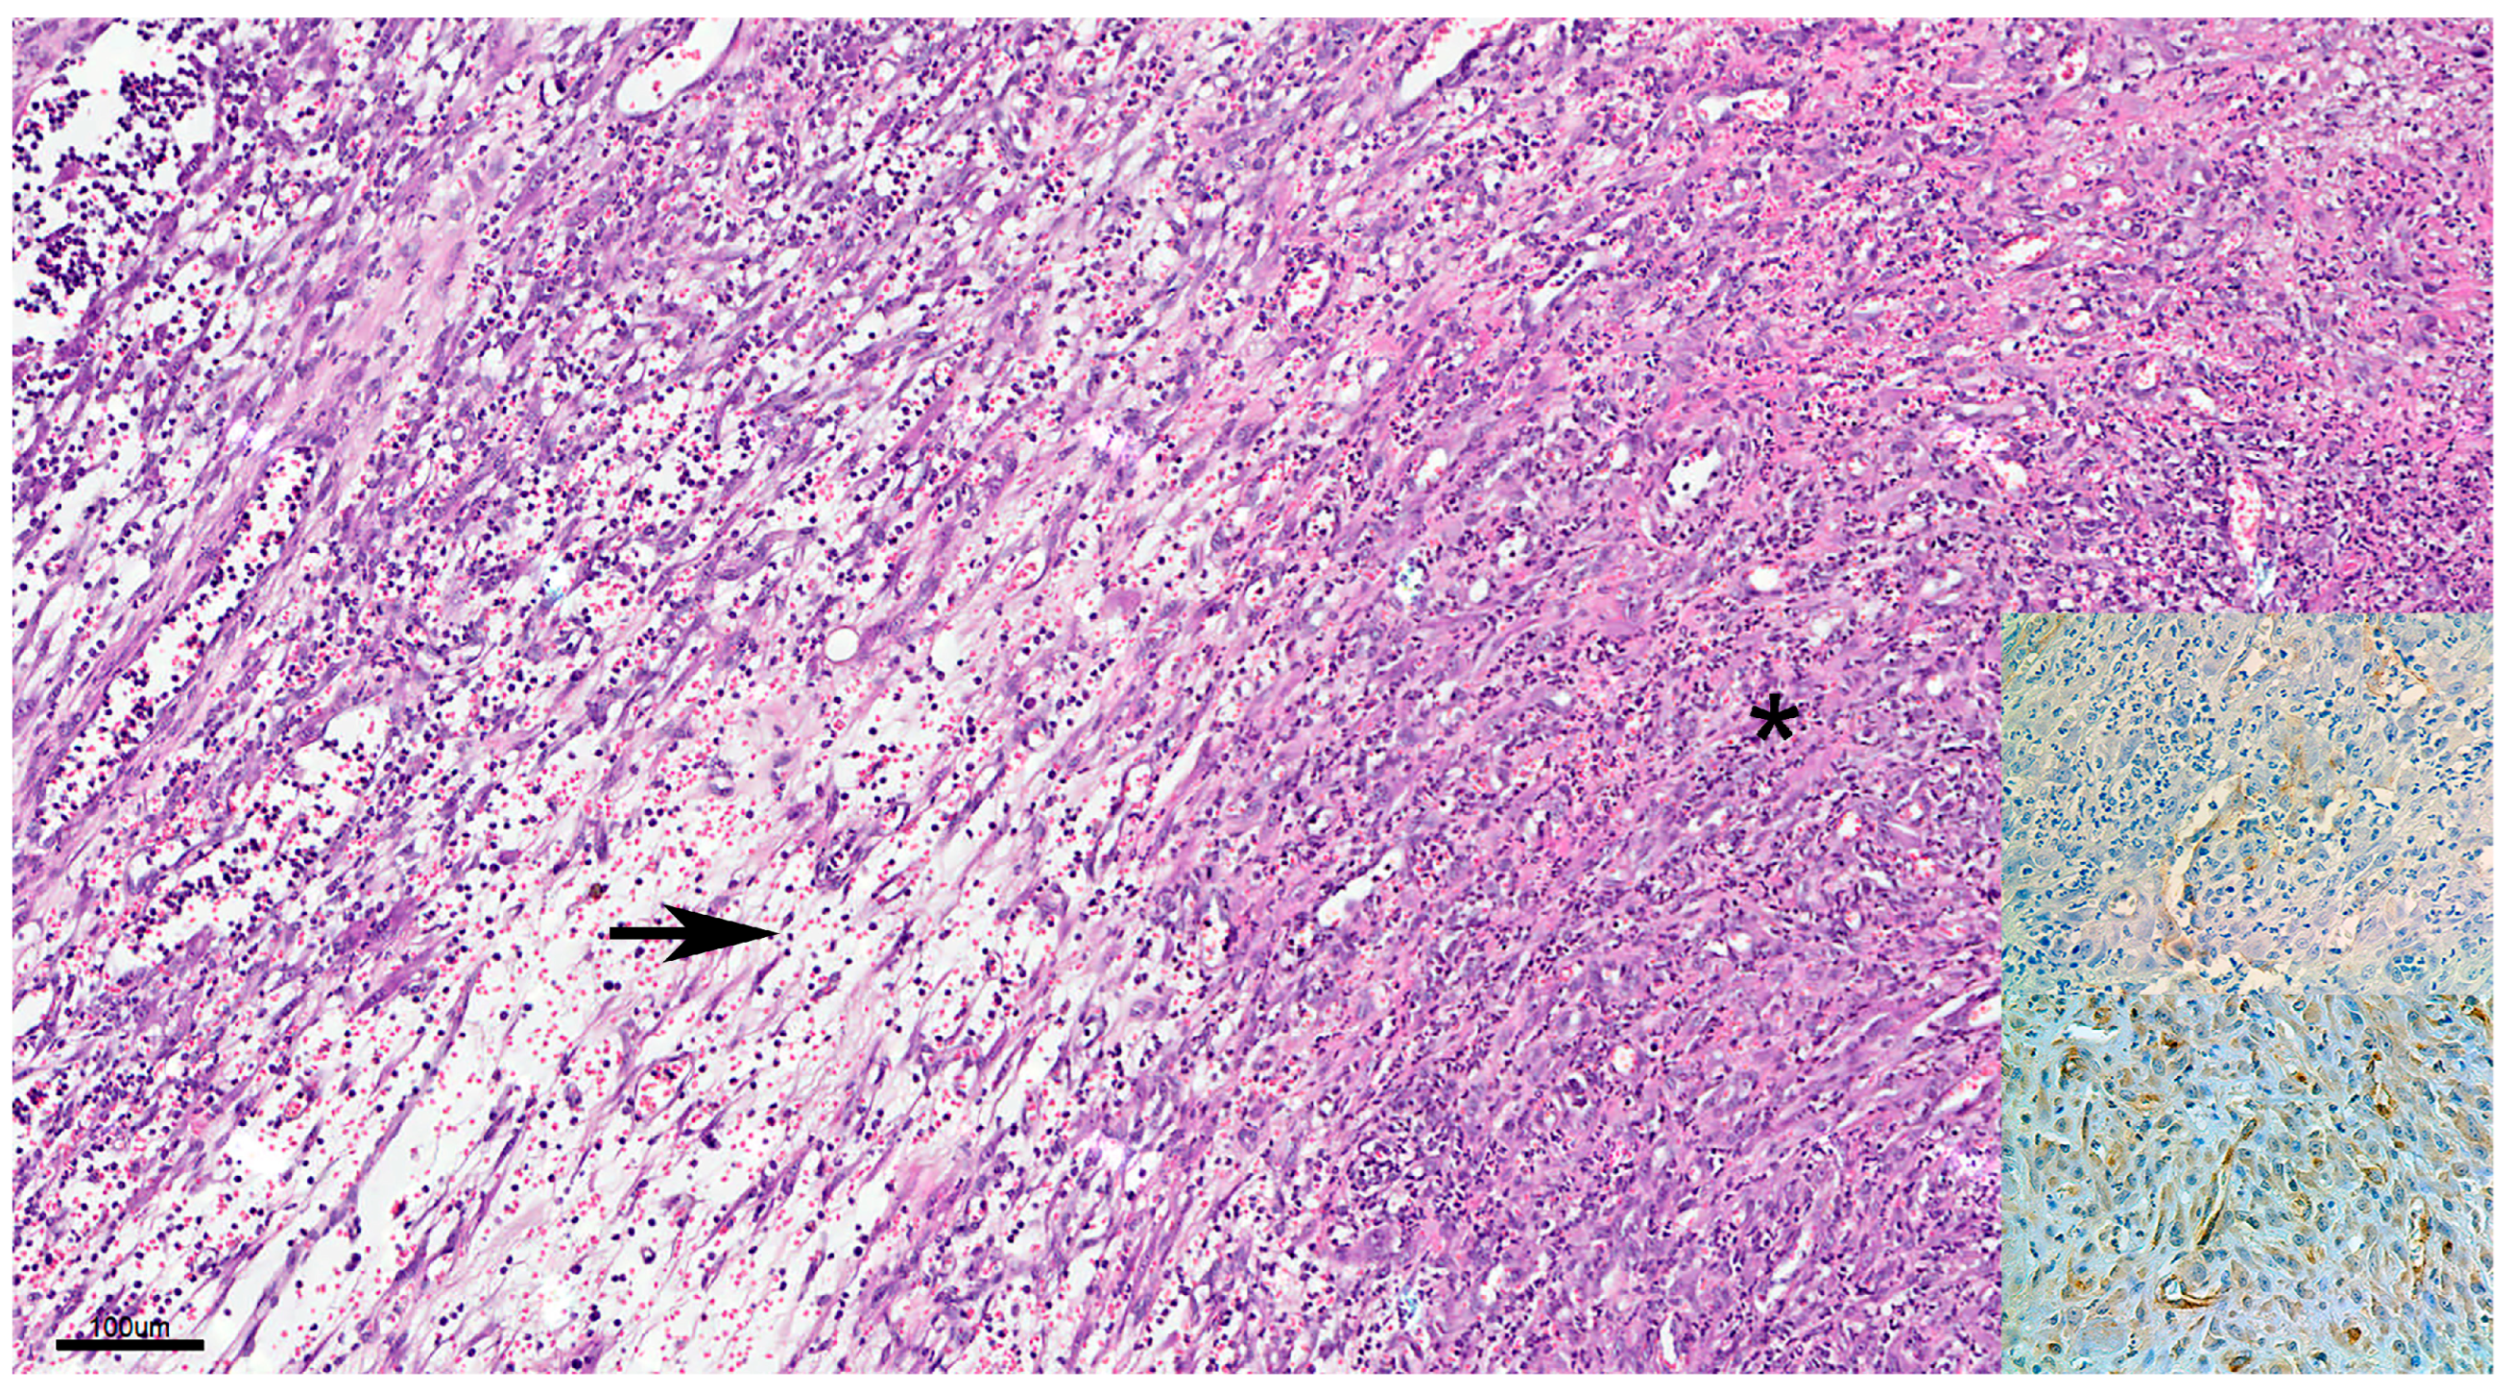

3.2. Hemangiosarcomas

3.2.2. Histopathology

3.2.3. Immunohistochemistry